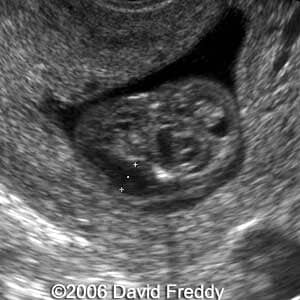

Cystic hygroma

David Freddy, MD

Israel

This is a 24-year-old-primigravida with a cystic hygroma diagnosed at 11 weeks and 5 days.